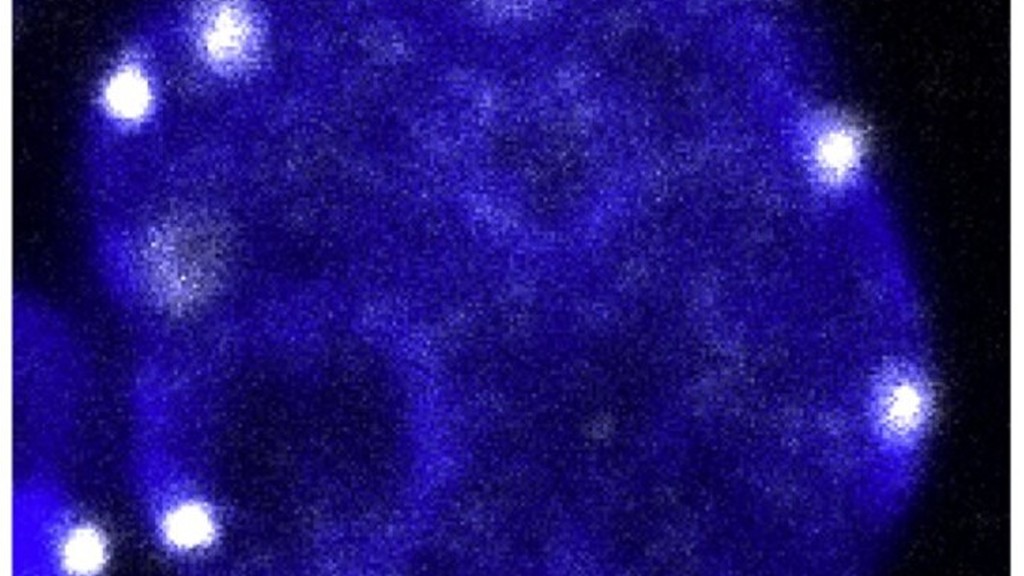

I risultati dimostrano che nel momento in cui la cellula germinale embrionale è pronta ad affrontare la meiosi (la divisione che dimezza il patrimonio genetico per generare i gameti, ovuli o spermatozoi), il centromero dei cromosomi, ovvero la struttura al centro dei loro quattro bracci , si sposta ai margini del nucleo della cellula e la struttura tridimensionale del Dna si 'rilassa'. Questo riposizionamento sembra fondamentale per la preparazione alla meiosi e non è mai stato riscontrato nei modelli cellulari coltivati in vitro , un possibile indizio sul perché sia così difficile replicare questo processo in laboratorio.